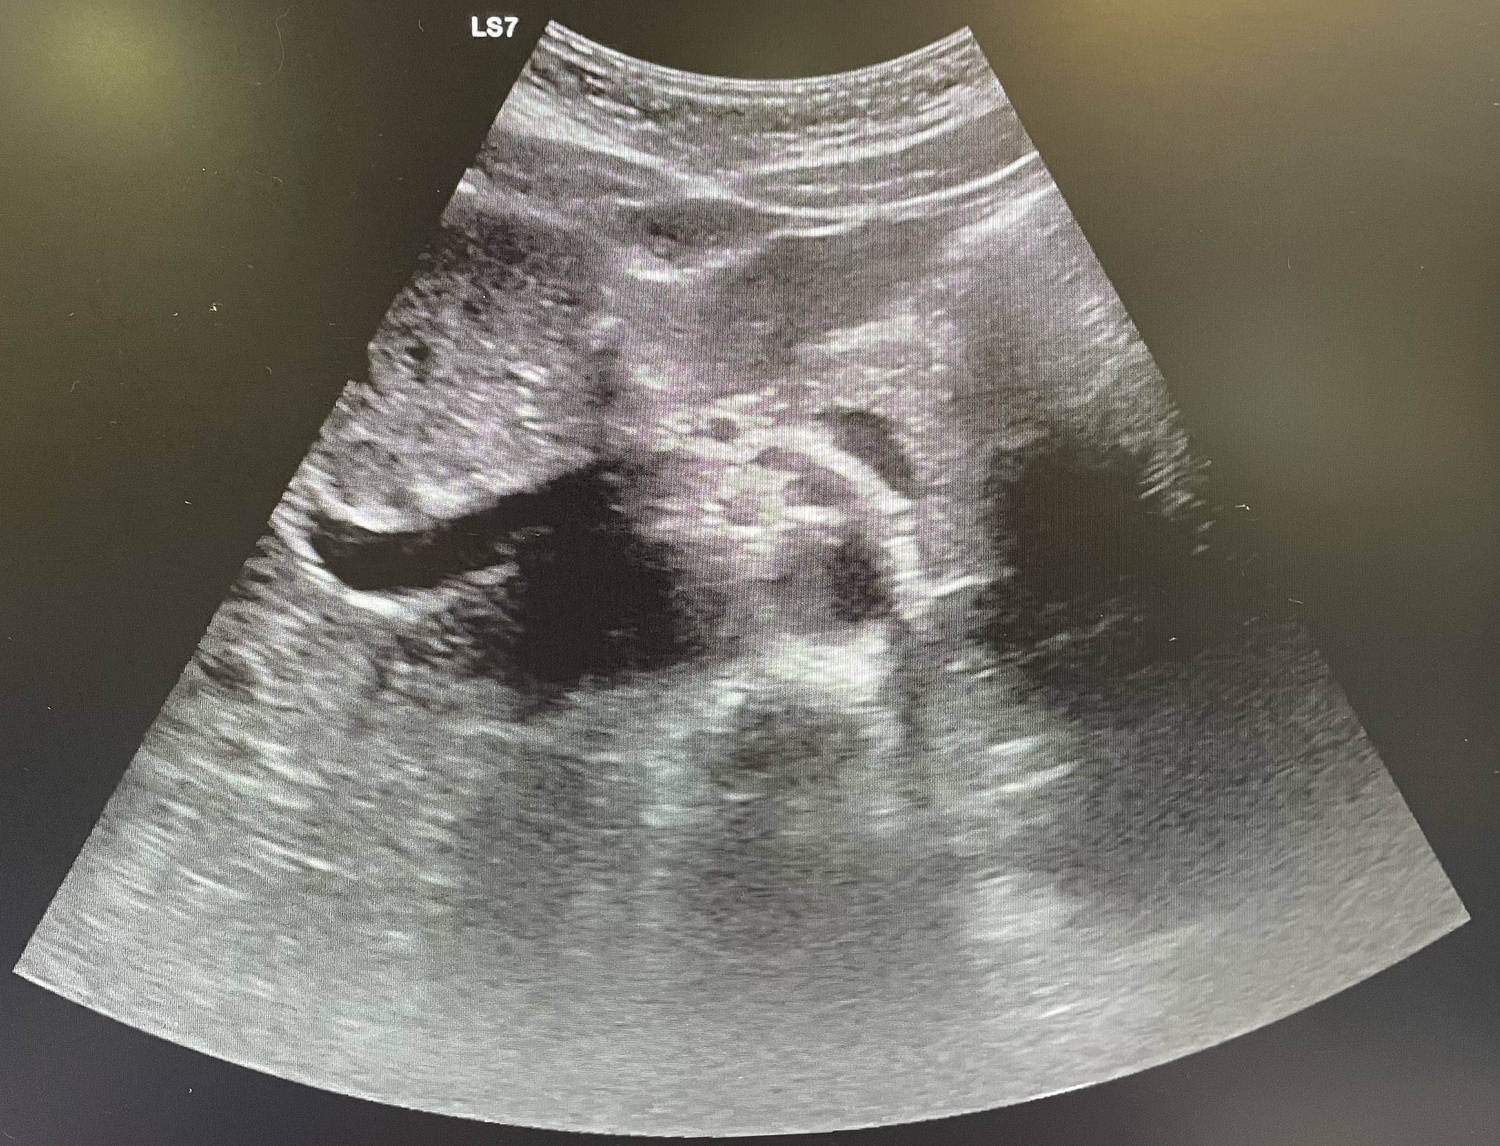

La paciente vuelve a acudir a urgencias con la misma sintomatología por lo que decide realizar TAC donde se observa apendicitis evolucionada, se contacta con cirugía que ingresa al paciente por plastrón apendicular.

Plastrón apendicular, con leves signos de peritonismo.